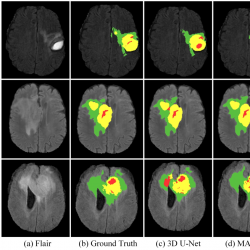

infor574_g007.jpg

Fig. 7

Visualization of segmentation results on the BraTS 2020 training set. WT contains red (labels 1), green (labels 2) and yellow (labels 4); TC contains red (labels 1) and yellow (labels 4); ET contains yellow (labels 4).

To better demonstrate the results of the method, Fig. 7 provides visual representations of select samples within the BraTS 2020 training set. Distinct colours correspond to varying label, with red signifying areas of necrotic and non-enhanced regions (label 1), green signifying areas of edema (label 2), and yellow signifying areas of enhancing tumour (label 4). The images describe the segmentation results of Flair, Ground Truth, 3D U-Net, and MAU-Net, respectively. In contrast to the 3D U-Net model, the figure underscores that MAU-Net excels in the segmentation of whole tumour (WT), tumour core (TC) and enhancing tumuor (ET) region.